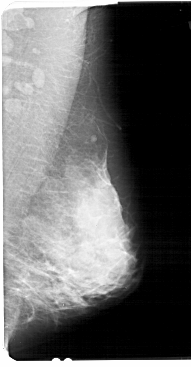

A_1449_1.LEFT_MLO

LEFT_MLO LINES 5491 PIXELS_PER_LINE 2776 BITS_PER_PIXEL 12 RESOLUTION 43.5 OVERLAY